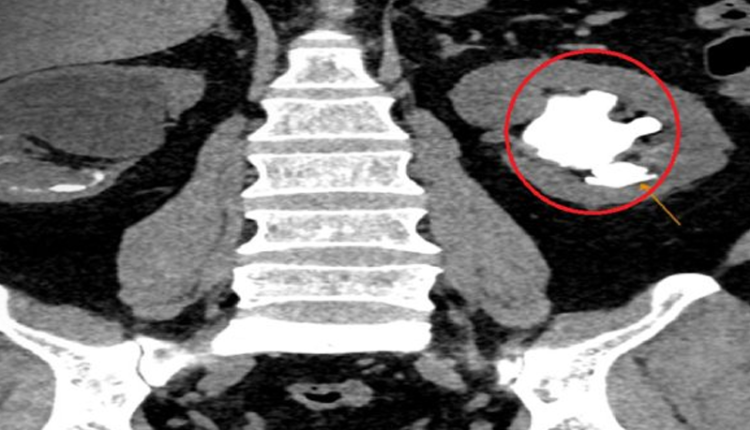

Sỏi san hô lấp đầy thận trái

Khối sỏi dài hơn 7cm như nhánh san hô lấp kín bể thận và các đài thận trái, bác sĩ phải mổ mở để lấy sỏi ra ngoài.

Ông T.V.T. (60 tuổi, ngụ Long An) đi khám sức khỏe định kỳ tại Bệnh viện Đa khoa Tâm Anh TP.HCM, phát hiện sỏi thận cả hai bên. Sỏi thận phải đường kính 3cm, gây ứ nước. Thận trái có khối sỏi san hô sần sùi, đường kính dài nhất hơn 7cm, lấp kín các bể thận và các đài thận lớn nhỏ. Viên sỏi chèn ép nhu mô khiến thận ứ nước nhẹ.

Bác sĩ CKI Lý Minh Hoàng, Trung tâm Tiết niệu – Thận học – Nam khoa, BVĐK Tâm Anh TP.HCM, cho biết thận người trưởng thành dài khoảng 11cm, ở thận ông T. viên sỏi san hô dài hơn 7cm. Trong trường hợp này, sỏi san hô lớn nhưng chưa gây biến chứng, như nhiễm khuẩn gây sốt, tiểu rắt hay cơn đau quặn thận do chèn ép… Tuy nhiên, nếu không phát hiện kịp thời, viên sỏi theo thời gian sẽ tăng kích thước, chèn ép nặng hơn vào nhu mô thận, gây giãn thận.